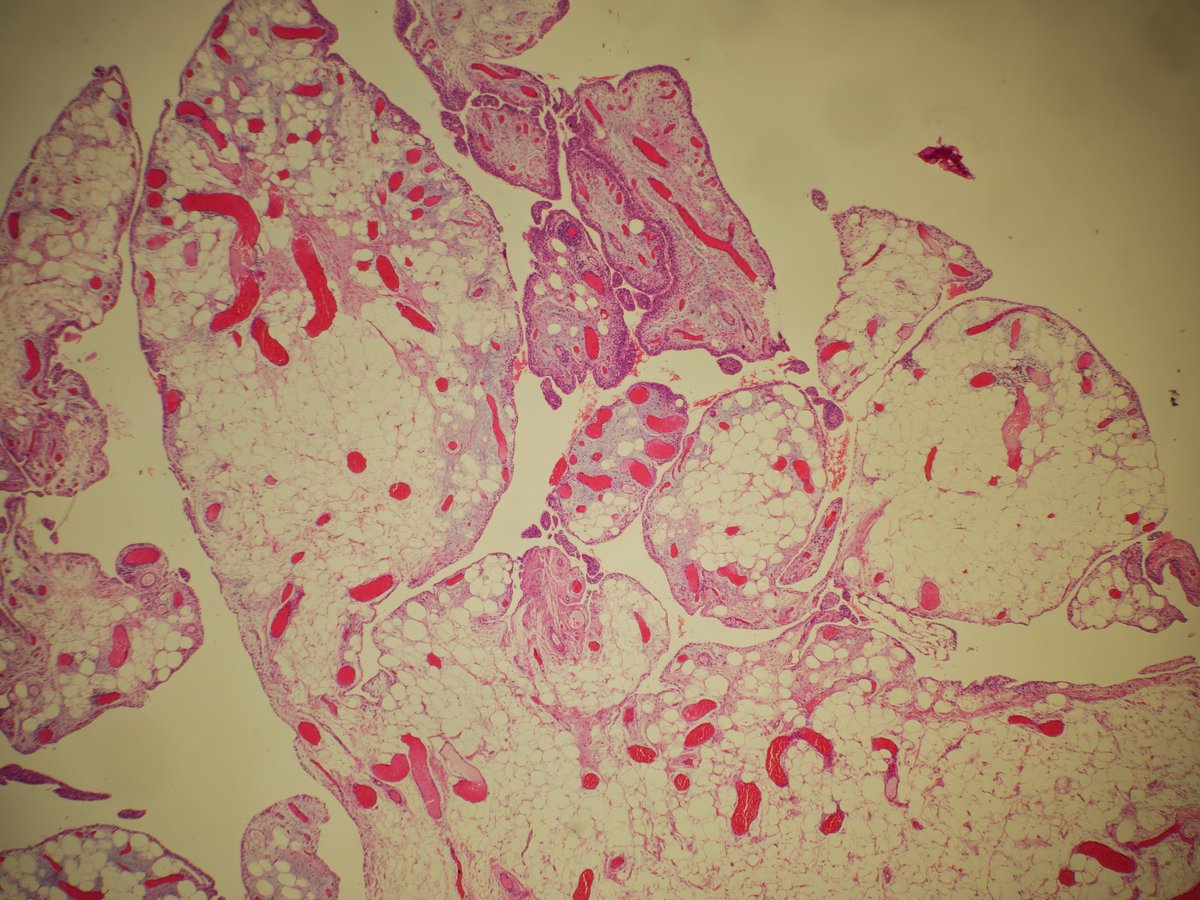

Synovial lipomatosis (lipoma arborescens, Hoffa's disease)

➡️Mature unremarkable fat extending to the partly hyperplastic synovial lining, imparting a villiform/papillary architecture

➡️Scattered chronic inflammation

➡️M>F, usually knee joint

#BSTPath #PathTwitter #pathoutpic